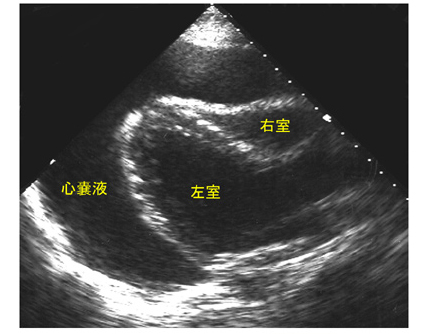

心嚢液が貯留して心臓を圧迫することにより心機能を障害する病態が心タンポナーデです。上行大動脈の急性解離、急性心筋梗塞では出血性の心嚢液貯留でショック、意識消失を来すこともあります。また、結核性、癌性、右心不全などでは無症状でゆっくり貯留するためレントゲンでの心拡大などで指摘される場合もあります(fig.8)。タンポナーデの典型的な症状として血圧低下、頚静脈怒張、心音減弱(Beckの三徴)が有名です。